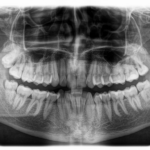

A fogászati állapotfelmérés során a legkorszerűbb diagnosztikai eszközökkel állunk rendelkezésére: panoráma röntgen, teleröntgen, kis röntgen és 3D CT – ezekről itt olvashat bővebben.